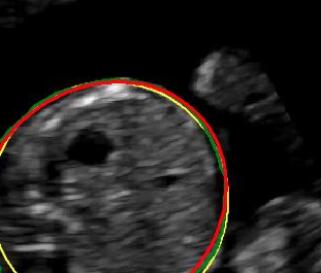

Sound-opaque occluders, including bones and calcified tissues, block the propagation of sound waves by strongly absorbing or reflecting sound waves during scanning. The regions behind these sound-opaque occluders return little to no reflections to the US transducer. Thus these areas have low intensity but very high acoustic impedance gradients at their boundaries (e.g. Fig. 1(a) left column). Reducing acoustic shadows and correct interpretation of images containing shadows rely heavily on sonographer experience. Experienced sonographers avoid shadows by moving the probe to a more preferable viewing direction during scanning or, if no shadow-free viewing direction can be found, a mental map is compounded with iterative acquisitions from different orientations.

We propose a novel method based on convolutional neural networks (CNNs) to automatically estimate pixel-wise confidence maps of acoustic shadows in 2D US images. Our method learns an initial latent space of shadow regions from images consisting of multiple anatomies and with global image-level labels (“has shadow” and “shadow-free”), e.g. Fig. 1(a). The basic latent space is then estimated by learning from fewer images of a single anatomy (fetal brain) with coarse pixel-wise shadow annotations (approximately of the images with global image-level labels), e.g. Fig. 1(b). The resulting latent space is then refined by learning shadow intensity distributions using fetal brain images so that the latent space is suitable for confidence estimation of shadow regions. By using shadow intensity information, our method can detect more shadow regions than the coarse manual segmentation, especially relatively weak shadow regions.

We propose a shadow-seg module to extract generalized shadow features for a large range of shadow types in fetal US images under limited weak manual annotations. Since shadow regions have different shapes, various intensity distributions and uncertain edges, the pixel-wise annotation of shadow regions is time consuming and relies heavily on annotator’s experience (e.g. various annotations in Fig. 1(b)). This generally results in manual annotations of limited quantity and quality. Compared with pixel-wise shadow annotations, global image-level labels (“has shadow” and “shadow-free” in our case) are easier to obtain, and shadow images with global image-level labels can contain a larger variety of shadow types. Therefore, we use a shadow-seg module that combines unreliable pixel-wise annotations and global image-level labels as weak annotations.The proposed shadow-seg module contains two tasks, (1) shadow/shadow-free classification using image-level labels, and (2) shadow segmentation that uses few coarse pixel-wise manual annotations ( of the global image-level labels). Shadow features can be extracted during simple shadow/shadow-free classification and subsequently optimized for the more challenging shadow segmentation task. In our case, shadow features extracted by the classification network cover various shadow types in a range of anatomical structures. These shadow features become suitable for the shadow segmentation after being optimized by a shadow segmentation network.